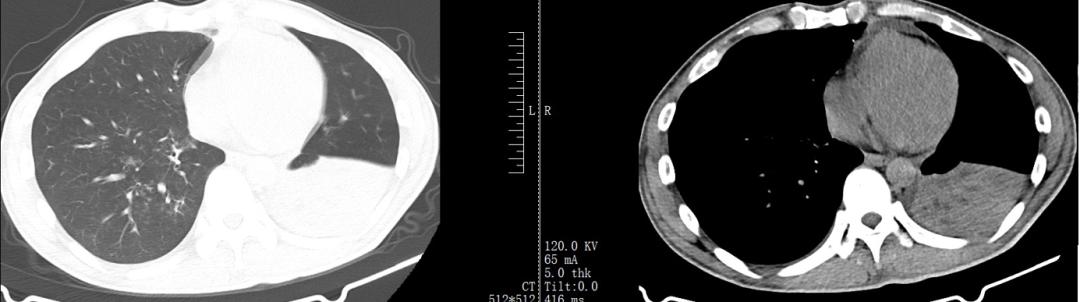

据肖先生自己回忆,刚开始发病时,他曾有过短暂的发烧,体温最高达38℃。但发烧并不规律,忽高忽低。起初他以为自己是上呼吸道感染,在当地医院开了头孢类抗生素进行治疗。治疗约1星期后,咳嗽不但未能减轻反而越来越明显,而且昼夜不停地咳。2022年1月13日和1月29日,肖先生分别在当地另一家医院做胸部CT,影像学显示他的气管分叉处有软组织影,食管的上、中段增厚(见图1、2)。

图1:肖先生2022年1月13日在当地某医院的胸部CT影像学

图2:肖先生2022年1月29日在当地某医院的胸部CT影像学